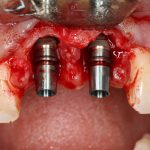

Рекомендации по установке имплантов. Для всех. Часть V.